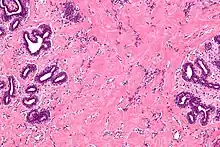

| High magnification micrograph of pseudoangiomatous stromal hyperplasia showing the characteristic small, anastomosing blood vessel-like channels. H&E stain. | |

Pseudoangiomatous stromal hyperplasia (PASH) is an overgrowth of myofibroblastic cells in the breast. It has an appearance similar to fibroadenomatoid changes.[1]

The important differential diagnosis is angiosarcoma, from which it was first differentiated in 1986.[2]